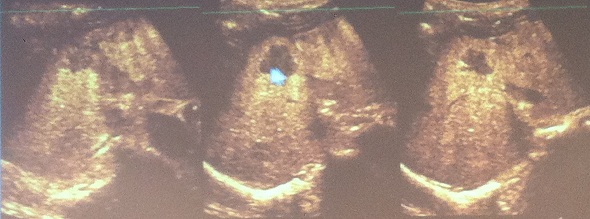

ÄíÆÛ¼¼Æ÷¸¦ Ȱ¿ëÇÑ ¿µ»ó¿¡¼ È®ÀεǴ °£¾Ï º´º¯ ºÎÀ§ |

ÄíÆÛ¼¼Æ÷¸¦ Ȱ¿ëÇϸé Á¶¿µCT¸¦ Ȱ¿ëÇØµµ ã±â ¾î·Á¿ü´ø 1cm ¹Ì¸¸ÀÇ º´º¯±îÁö ã¾Æ³¾ ¼ö ÀÖ¾î °£¾Ï Á¶±âÁø´ÜÀº ¹°·Ð Ä¡·á°úÁ¤°ú Ä¡·á ÈÄ °Ë»ç¿¡¼µµ Á¶¿µÃÊÀ½ÆÄ°¡ È¿°úÀûÀ¸·Î Ȱ¿ëµÉ ¼ö ÀÖ´Ù.